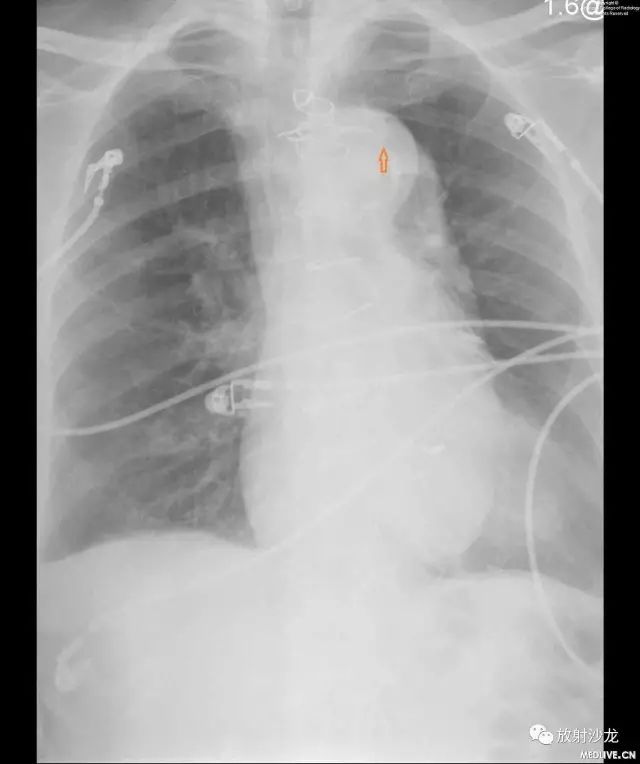

图1和图2:图像显示主动脉结移位。图1是患者一两个月前在另外一次主诉不同的随访中进行的检查结果。与图1相比,图2的移位显而易见。

由于IMH与其他常见疾病症状存在重叠,诊断主要依赖于影像学检查。对有胸痛这一非特异性症状的患者进行初步检查时,胸片显示纵膈影增宽往往是最常见的发现,可见于61.6%的患者。主动脉钙化移位是最不常见的发现,在14.1%的患者中可以看到, 12.4%的患者胸片没有任何特殊表现。尽管它敏感性和特异性均很低,但胸片往往能够提供细微线索,以提示进一步的全面评估和诊断,正如本病例所示。